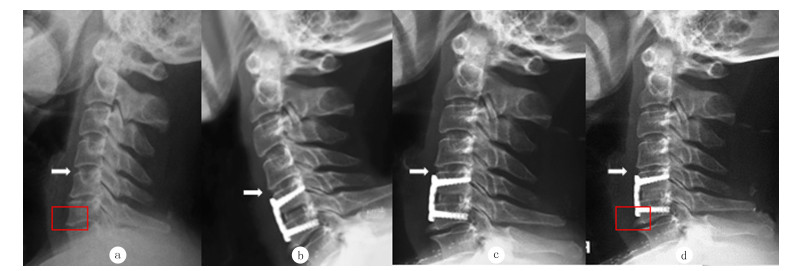

2 结果术后随访2年,ASD的发病率为23.3%(14/60)。1例病人ASD影像表现见图 1。根据末次随访时融合椎体邻近节段是否发生ASD,将病人分为无退变组(A组)和ASD组(B组),ASD组与无退变组病人性别、椎管直径比较差异无显著性(P>0.05);ASD组年龄大于无退变组,术后Cobb角和PDD均小于无退变组,差异有显著性(t=-8.12~2.83, P<0.05)。见表 1。

| 病人,女,70岁,入院诊断为C5/6椎间盘突出症,行ACDF、钛板联合Cage固定术。a为病人术前X线图像;b为病人术后3 d的X线图像;c为病人术后12个月随访时X线图像;d为病人术后44个月随访时X线图像。白色箭头指示邻近椎间隙变窄,红色标记提示邻近节段明显骨赘形成。 图 1 1例C5/6椎间盘突出症行ACDF病人ASD影像表现 |